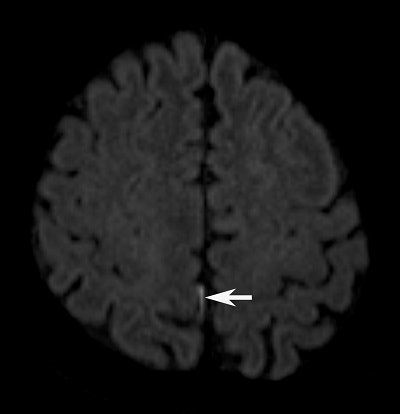

Thirteen (93%) of the subjects had abnormal findings, including increased hyperintensities in the brain parenchyma, subarachnoid space, and ventricles on DWI scans.

DWI hyperintensities in the brain parenchyma suggest the possibility of cerebral infarction, the authors noted, and were evident within 10 days of symptom onset. Abnormalities in the subarachnoid space and lateral ventricles are consistent with meningitis caused by GBS.

DWI also found uncommon hyperintensities in the cerebellum of five patients, detecting lesions as small as 7 mm and as large as 42 mm. Interestingly, lesions in the brain parenchyma, subarachnoid space, ventricles, and cerebellum were not visible on T2-weighted or FLAIR images or with the addition of contrast.

"We were a bit surprised to discover central nervous system MRI changes in patients who ate contaminated raw fish, rather than gastrointestinal abnormalities," Lim said. "In most cases, DWI was the only abnormal finding when all else looked normal, especially to detect small amounts of pus in the ventricles and subarachnoid space."